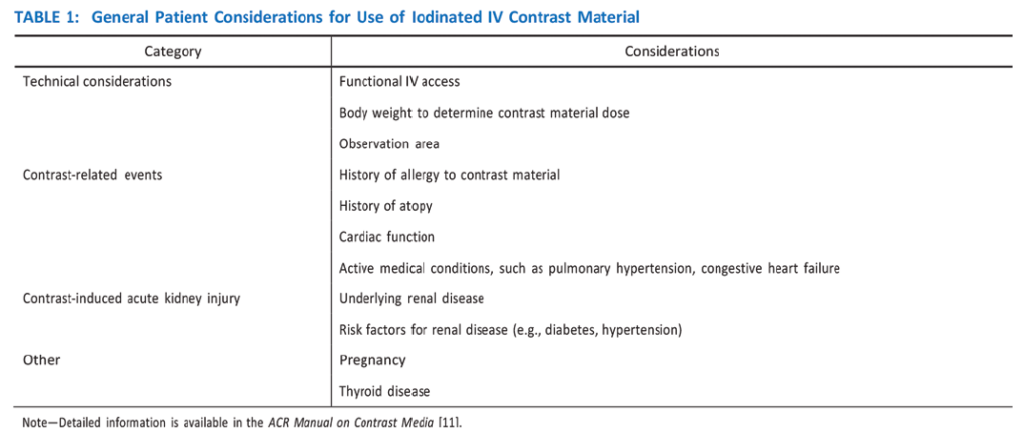

Sternoclavicular Joint

Athletic injuries to the sternoclavicular joint may lead to anterior dislocation (more common and less concerning) or posterior dislocation [11, 12]. The latter phenomenon is less frequent, but more concerning, because the clavicular head has the potential to exert mass effect on the great vessels, trachea, esophagus, and recurrent laryngeal nerve (causing vocal cord palsy). Posterior dislocations require 50% more force to occur, compared with anterior dislocations. This is because the capsular structure of the sternoclavicular joint is more robust posteriorly [13]. Posterior sternoclavicular joint dislocations are most commonly related to direct-force injuries seen in football, rugby, martial arts, and motor vehicle accidents (typically motorcycle accidents). Sternoclavicular dislocations can be imaged by CT and/or MRI, both of which may show malalignment at the joint with associated fractures or hematomas from capsular disruption. In the case of posterior dislocations, CT provides excellent delineation of the joint alignment, and use of IV contrast material allows assessment of the integrity of adjacent vascular structures. Alignment of mediastinal structures and possible hematomas are also best seen on CT. The initial treatment of posterior sternoclavicular dislocations includes attempted closed reduction, which is usually performed under sedation as an urgent procedure. If this procedure fails to realign the joint, or if the joint remains unstable, a surgical approach involving open reduction and internal fixation may be necessary.